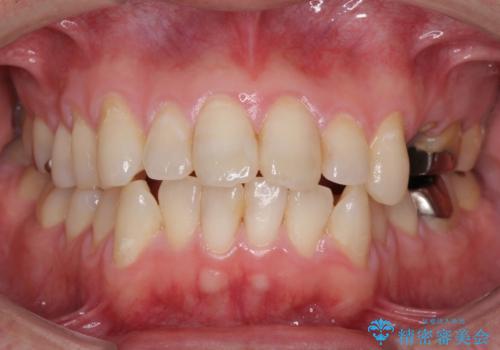

[ 金属アレルギー ] 銀歯を除去するメタルフリー治療

担当医 大元洋佑